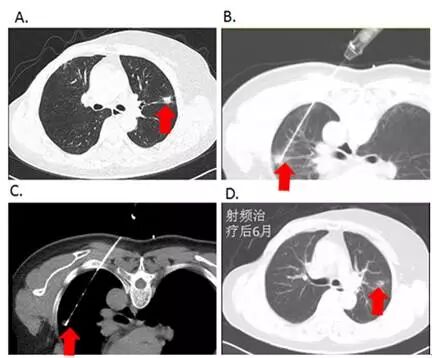

图1:CT引导下肺恶性肿瘤射频消融治疗

用于肺转移瘤的治疗。研究表明,肺转移瘤且直径≤2-3cm,接受RFA治疗的肺转移瘤患者,3年生存率为53.7%,4年生存率为44.1%。如图3所示,1例乳腺癌患者术后复发伴左肺单发转移,经RFA治疗后复查及随访近3年,生活质量良好,无远处复发。

图3:患者,女性,48岁,乳腺癌术后单发肺转移。